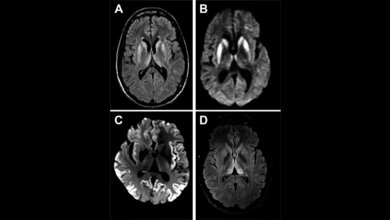

Prion-Erkrankungen sind eigentlich sehr selten. Etwa zwei von einer Million Menschen sind davon betroffen. Im Verlauf der Krankheit nimmt das Gehirn eine schwammartig durchlöcherte Struktur an und weist proteinhaltige Ablagerungen auf. „Auslöser der Erkrankungen ist die fehlerhafte Faltung des zellulären Prion-Proteins, kurz PrP, im Gehirn“, erklärt Prof. Dr. Jörg Tatzelt vom Institut für Biochemie und Pathobiochemie an der Ruhr-Universität Bochum, der die Studie leitete. „Die krankhaften Eiweiße lagern sich im Gehirn ab und bilden verklumpte Ablagerungen, sogenannte Plaques. Die Funktion der Nervenzellen wird dadurch zunehmend gestört.“ Nachgewiesen wurden Prion-Erkrankungen bisher ausschließlich bei Säugetieren. Grundsätzlich kommen Prion-Proteine aber auch in den Gehirnen von Fröschen und Reptilien vor.